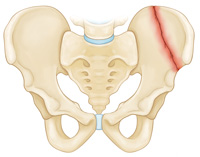

Iliac wing fracture

Sacrum fracture

The pelvis helps anchor the muscles and protect the organs in the lower abdomen.